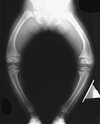

**Obtain serum phosphorous, calcium, and alkaline phosphatase levels.** ## Footnote radiograph shows multiple wide physes, consistent with a diagnosis of rickets. A low serum phosphorous level and an elevated alkaline phosphatase level are the hallmarks in diagnosing familial hypophosphatemic Vitamin D-resistant rickets. Serum calcium is usually normal or low normal. This disease is inherited as an X-linked dominant trait and usually presents at age 18 to 24 months. The disease results from a poorly defined problem with renal phosphate transport in which normal dietary intake of vitamin D is insufficient to achieve normal bone mineralization. Renal tubular dysfunction is associated with urinary phosphate wasting. Treatment involves oral phosphate supplementation, which can cause hypocalcemia and secondary hyperparathyroidism. To prevent associated problems, high doses of Vitamin D are administered. While obtaining a scanogram may be clinically indicated in an associated limb-length discrepancy, and subsequent corrective surgery may be indicated, either of these choices would not be the first course of action. An orthosis may slow the progression of genu varum in this disorder but is less important than establishing the correct diagnosis to begin pharmacologic treatment. This amount of varum and tibial bowing far exceeds the normal limits of physiologic genu varum. Skeletal dysplasias usually are not associated with abnormal laboratory values.

radiograph shows multiple wide physes, consistent with a diagnosis of rickets. A low serum phosphorous level and an elevated alkaline phosphatase level are the hallmarks in diagnosing familial hypophosphatemic Vitamin D-resistant rickets. Serum calcium is usually normal or low normal. This disease is inherited as an X-linked dominant trait and usually presents at age 18 to 24 months. The disease results from a poorly defined problem with renal phosphate transport in which normal dietary intake of vitamin D is insufficient to achieve normal bone mineralization. Renal tubular dysfunction is associated with urinary phosphate wasting. Treatment involves oral phosphate supplementation, which can cause hypocalcemia and secondary hyperparathyroidism. To prevent associated problems, high doses of Vitamin D are administered. While obtaining a scanogram may be clinically indicated in an associated limb-length discrepancy, and subsequent corrective surgery may be indicated, either of these choices would not be the first course of action. An orthosis may slow the progression of genu varum in this disorder but is less important than establishing the correct diagnosis to begin pharmacologic treatment. This amount of varum and tibial bowing far exceeds the normal limits of physiologic genu varum. Skeletal dysplasias usually are not associated with abnormal laboratory values.